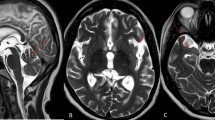

At the time of dementia onset, EEG background activity showed mild generalized slowing. The intermittent photic stimulation (IPS) at 1–30 Hz was normal. Physiological sleep patterns were always detected. In four patients (1, 2, 3, and 9) the sleep patterns were associated with sporadic diffuse spike-and- wave (SW) or polyspike-and-wave (PSW) discharges ( Fig. 1).

Stage 1: dementia onset. In the upper panel, EEG recordings in patients 1, 2, 3, and 9 are shown. Sleep revealed stereotypical EEG abnormalities in different patients. In the lower left panel, polygraphic recording are shown from patient 3 that are characterized by epileptiform abnormalities during sleep and that were not associated with myoclonic jerks (R. and L. Flex right and left flexor muscles of the hand, R. and L. Ext right and left extensor muscles of the hand, R. and L. Tib. A right and left muscles of the tibialis anterior). In the lower right panel, CT images of the brains of patients 3 and 11 reveal diffuse cerebral atrophy

Brain MRIs/CTs revealed diffuse cerebral atrophy in all patients (Fig. 1), that was associated with noncommunicating hydrocephalus in patient 8.